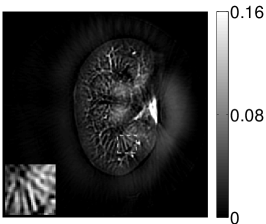

Figure 2(a) shows the image reconstructed by use of the conventional iterative method that utilized a system matrix based on EIR-2. Different values of the regularization parameter from the interval were considered. The reconstructed image with the value of that minimized the RMSE was chosen to represent the best performance of the conventional iterative method. Figure 2(a) and the profile in Figure 2(c) demonstrate that the use of an inaccurate EIR can result in strong artifacts and distortions in images reconstructed by use of the conventional methods.

When the VP algorithm was applied, different values of the regularization parameter from the interval and from the interval were considered. The image that minimized the RMSE was chosen and displayed in Figure 2(b). As revealed by this image and the profiles in 2(c), the VP algorithm yielded an image with fewer artifacts and distortions, and image fidelity was improved as reflected by the reduced RMSE.

The images and EIRs reconstructed by use of the VP algorithm that was based on the 2D imaging model that neglected the SIR are shown in Figures 15 and 16. The latter figure contains results corresponding to different values for the regularization parameter . From Fig. 15, it can be observed that use of the conventional iterative method that utilized the measured EIR resulted in distortions and loss of details in the reconstructed images. Use of the VP algorithm improved the contrast and the details in the reconstructed images (Fig. 15(c) and 16(a)). Furthermore, the images reconstructed by use of the VP algorithm had a more uniform background.

In Figure 17, the results corresponding to use of the 3D imaging model that incorporated SIR effects are shown. The EIR estimated by the VP algorithm is also shown. In Figure 18, images and EIRs reconstructed by use of the VP algorithm with different regularization parameters values are shown.

Similar to the case described above where the transducer SIR was neglected, these results reveal that use of the VP algorithm can produce images with a cleaner background and enhanced spatial resolution than yielded by use of a conventional iterative algorithm that employed the measured EIR. For example, detailed information regarding the vessels near the organ’s periphery was better preserved by the VP algorithm than by the conventional iterative algorithm. These images corroborate our assertion that the VP algorithm can significantly reduce the artifacts and distortions in the reconstructed image. It is also worth pointing out that, unlike the numerical phantom studies, the artifacts and distortions in the images may be caused not only by the inaccurate EIR but also by other factors, such as neglecting acoustic heterogeneities and the variation of the EIRs among the elements of the transducer array. In such cases, the EIR estimated by the VP algorithm represents an effective system impulse response that minimizes the inconsistency between the measured data and the imaging model.